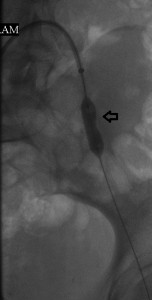

I present here a young woman whose primary care physician referred to me because of acute pain in her left great toe that was associated with discoloration. Her left common femoral pulse was diminished on examination and its waveform abnormal on arterial Doppler sonography. The image to the far left of the reader shows a focal filling defect of the distal left common iliac artery with sharp margins between its upper and distal surfaces and the vessel lumen, a calcified plaque from which a small embolus may have arisen. The rest of her angiography was normal. The middle image shows the deployment of a short balloon-expandable stent across the filling defect, while the image to the reader’s right is the post-intervention study that shows restoration of normal blood flow through the left iliac channel. Her symptoms resolved and she returned to her primary care provider on aspirin, Plavix, and advice to quite smoking, while pursuing hypercoagulability workup with him.